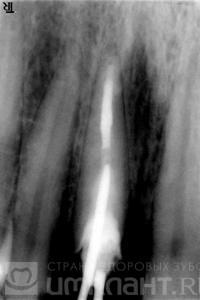

Cu toate acestea, atunci când studiază razele X, devine clar că rădăcina este suficient de lungă, că nu există nici o inflamație în partea superioară.

După 2 săptămâni, sa efectuat un tratament endodontic repetat, a fost instalat un știft din fibră de sticlă.